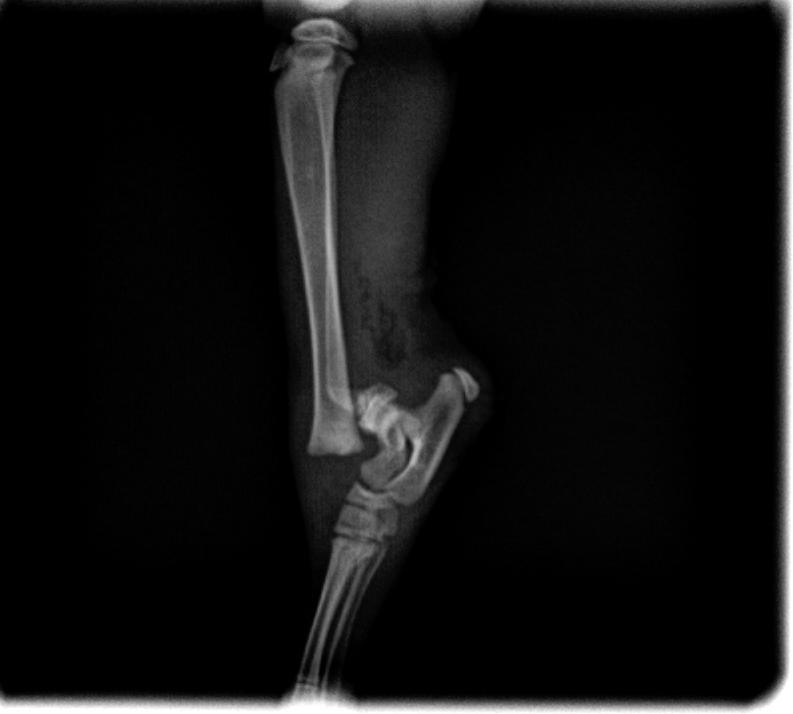

辛巴是一隻流浪小貓。在2016年12月被發現在垃圾收集站被狗咬傷,令他的右後腿嚴重骨折,傷口亦很深。善良的社工黃先生找到了他,並聯絡了Jack’s Veterinary。我們的獸醫Dr. Vincent Tse為了救回他,第一時間安排辛巴做手術。鰂魚涌獸醫診所的Dr. Jason Yew得知這個個案後,也很樂意借出手術房和設備。

手術前後的X光片對比,手術前可見明顯骨折,手術用鋼釘固定骨折位置

辛巴穩定後,兩位醫生很快就替他進行手術。手術非常順利。他在康復期間恢復得非常快。現在他長大了一點,走路跑步沒有任何問題,非常活躍。最高興的是,他後來獲一位非常愛錫他的主人收養,命名為辛巴。